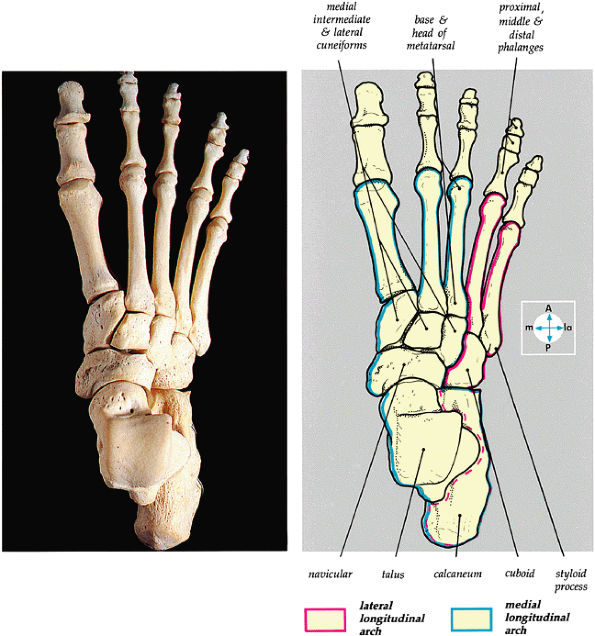

The medial and lateral longitudinal arches are formed by the tarsal and metatarsal bones (Fig. 5.80). The higher medial arch, which forms the instep of the foot, consists of the calcaneus, the talus, the navicular, the three cuneiform bones, and the medial three metatarsals (see Fig. 5.80; Fig. 5.81). The plantar calcaneonavicular (i.e., spring) ligament helps support the head of the talus, which articulates with the navicular anteriorly and the sustentaculum tali posteriorly (Fig. 5.82). The lateral arch consists of the calcaneus, the cuboid, and the lateral two metatarsals.

FIGURE 5.80 ● The dorsal aspect of the bones of the foot shows the medial and lateral longitudinal arches.

FIGURE 5.81 ● (A) The medial aspect of the bones of the foot shows the medial longitudinal arch (blue). (B) The transverse arch of the foot in coronal section at the level of the first metatarsal sesamoids.